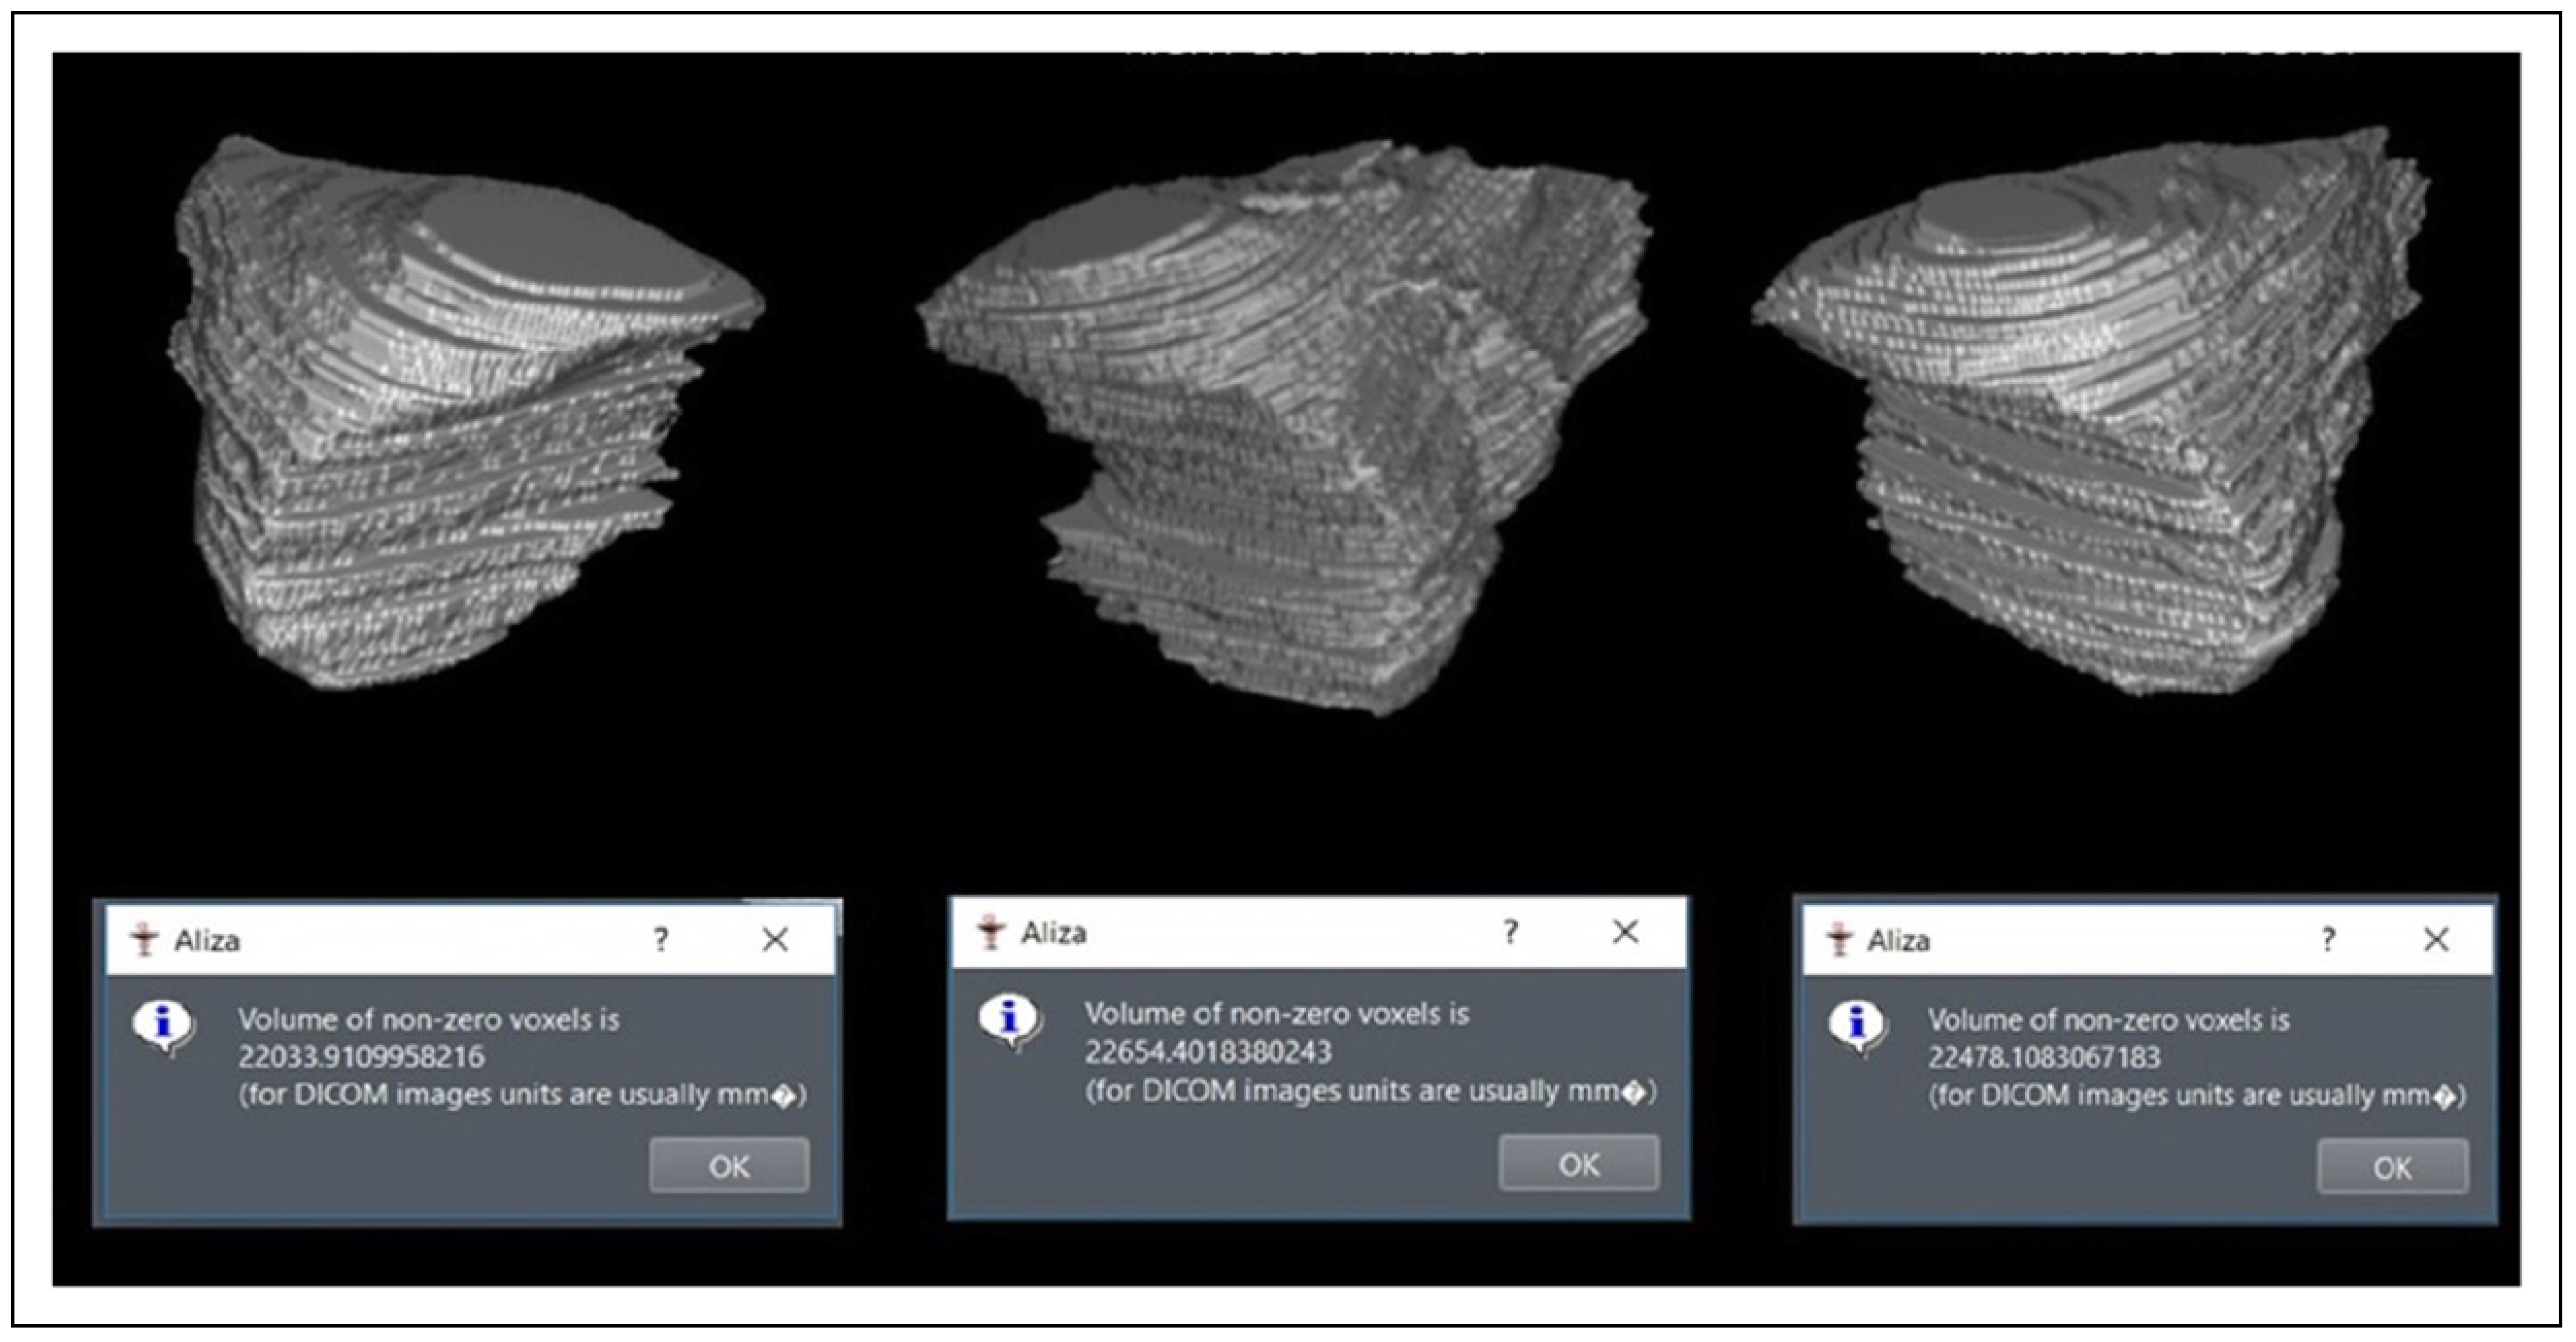

- After completion of manual segmentation of the concerned orbit, the ROI is selected and converted to a binary image. The volume was computed automatically by the software in mm3 (Figure 3) and then converted to cubic centimeters.